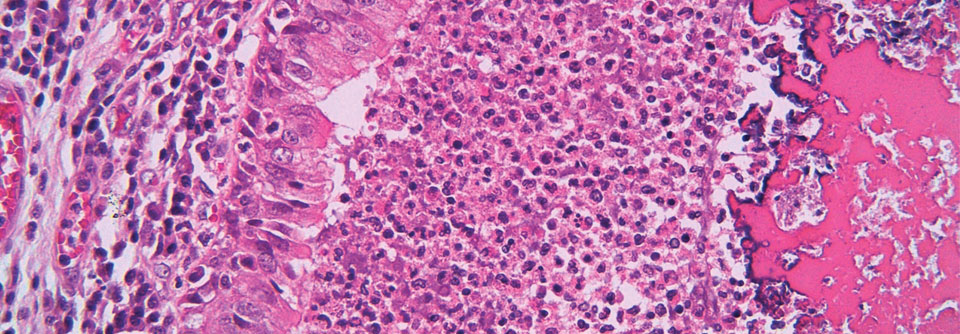

Dass eine Fibrose und ein Emphysem im klinischen Alltag gemeinsam auftreten können, war schon lange bekannt, als französische Forscher 2005 der Erkrankung den Namen CPFE (combined pulmonary fibrosis and emhysema) gaben. Anhand der HRCT-Befunde von 61 Teilnehmern einer multizentrischen Studie definierten sie die CPFE als Kombination aus einer signifikanten Fibrose – prädominant in peripheren und basalen Lungenanteilen – und einem oberlappenbetonten Emphysem.